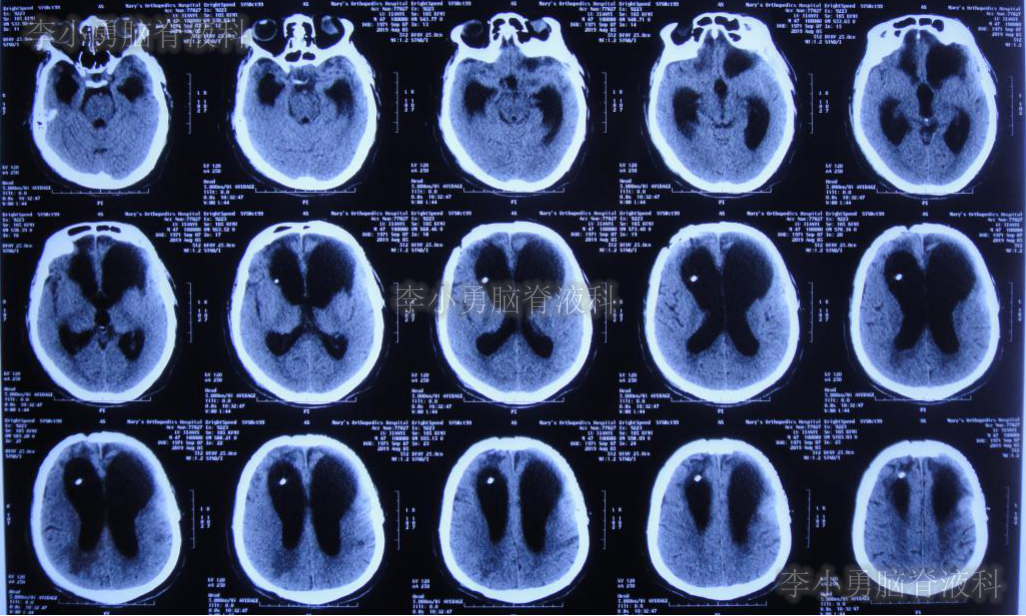

分流术后10天,即2019年10月9日,饮食变正常,神志完全清楚(图-18),常规给予复查头颅CT(图-19)示脑室进一步缩小。

图-19:2019年10月9日头颅CT脑室进一步缩小

出院后54天即2019年12月9日,复查头颅CT示脑室进一步缩小。患者智力、走路变得基本正常,但存在情感(喜怒哀乐不能表达)缺失,言语少(图-20)。

图-20:头颅CT脑室再次进一步缩小